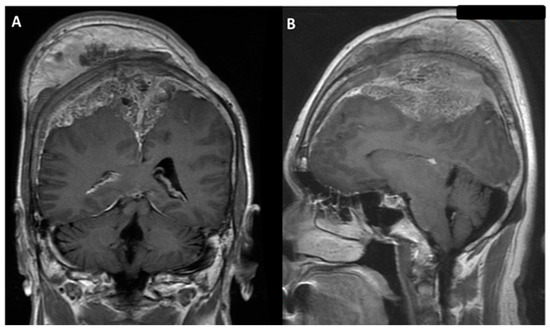

| Tsai et al., 2021 | 55/M | Seizure, loss of consciousness | 91 | bilateral | occluded | II | I | 2/5 left arm and left leg 0/5 right leg | Preserved | Aphasia | Aphasia recovery within 7 days; muscle power recovery within 7 weeks |